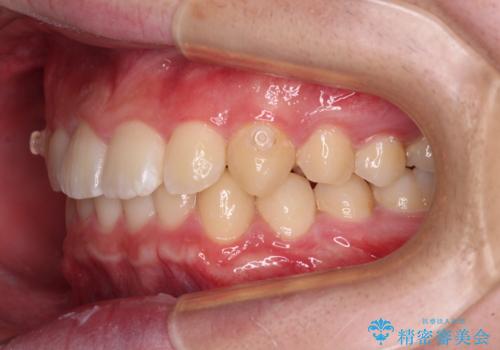

- 前方に傾斜した前歯を気にして来院された患者様です。

強く食いしばってしまう癖があり、下顎前歯に押し出されて上顎前歯が前方へ斜めに突き出している状態でした。

IPR(歯と歯の間を削る)を多用して、インビザラインにて矯正治療を行うこととしました。

口元を引っ込めるためのゴムかけを頑張っていただき、満足のいく上顎前歯の傾斜へ改善することができました。